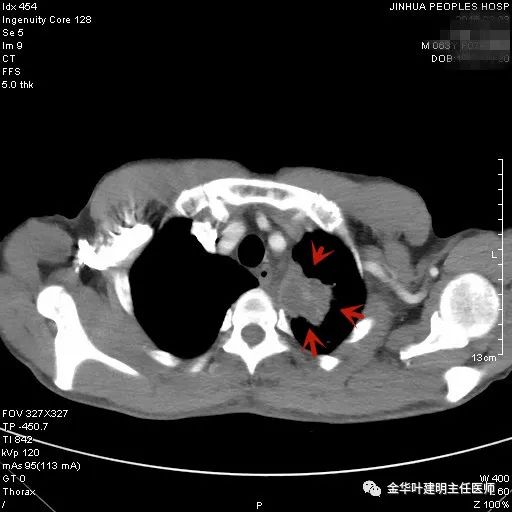

上图示慢性炎结节。我们见其桔色箭头示长毛刺征,绿色箭头示有血管贴边,但进出病灶的血管粗细相对没有什么改变(说明没有被病灶窃取多少血供),整体病灶边缘偏模糊。